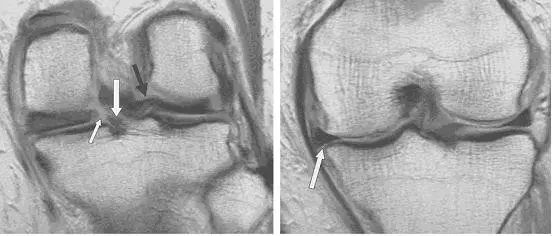

图 11 内侧半月板桶柄状撕裂——双后交叉韧带征

左图:经髁间切迹的矢状面,可见剥离开的低信号半月板块(白色箭头)平行于正常的后交叉韧带(黑色箭头)。右图:冠状面可见剥离的半月板块(白色直箭头),在正常的后交叉韧带(黑色箭头)下方。残留的半月板外缘(白色圆箭头)形态异常且比正常(对侧)的小。